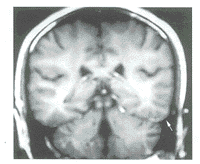

图1 正常成人冠状位增强扫描T1加权像

脑膜无强化(箭头)